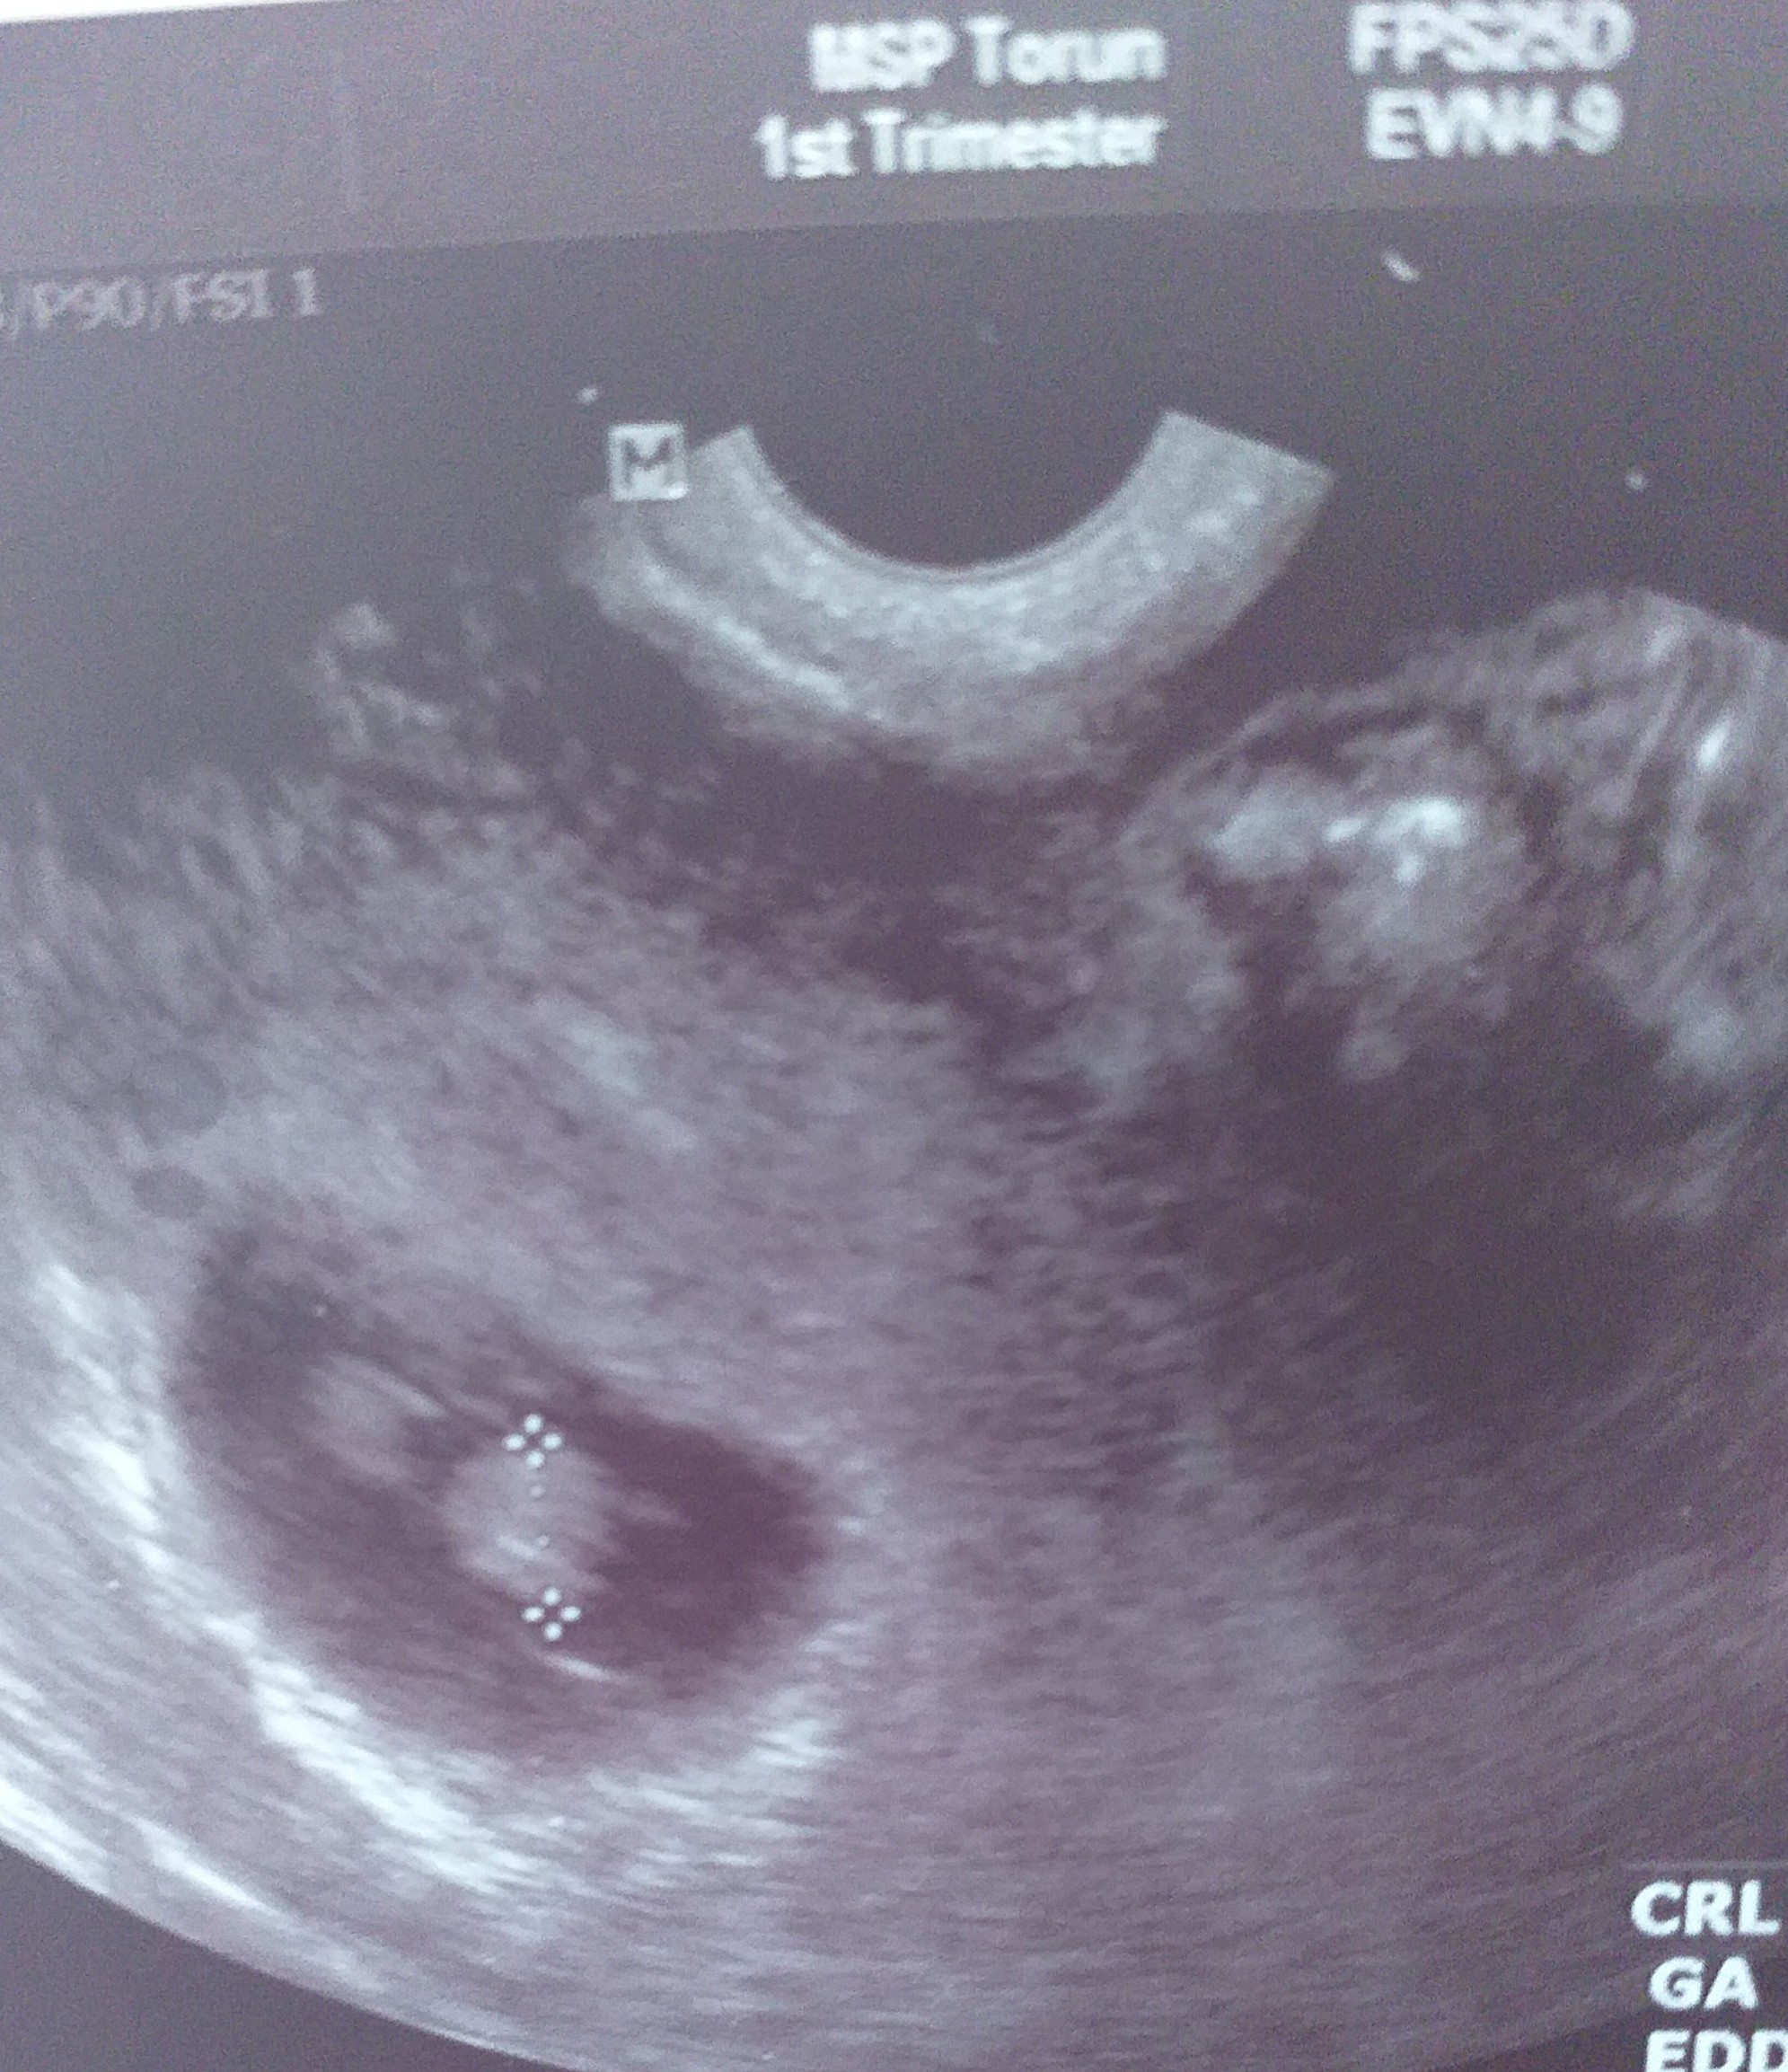

Mam pytanie najlepiej do mam bliźniąt, na zdjęciu usg widać jakby drugi płód. Jednak lekarz wpisał ciąża pojedyncza, zdjęcie usg z 7tygodnia +6dni. Dodam, że to moja druga ciąża lecz w czasie pandemii poszłam do pani ginekolog, która akurat miała termin i to co robiła było jakby z przymusu. Przechodząc do sedna, czy "to coś " widoczne w prawym górnym rogu to drugi płód? Jeśli nie to co to może być?